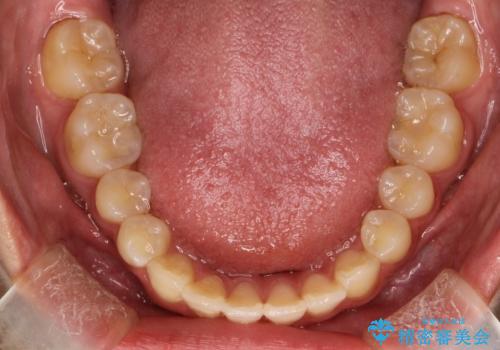

上あごの2番目の歯は矮小歯といって、生まれつき小さい歯となる事がよくあります。

このような場合、矯正によりスペースを集め、本来あるべき形態にセラミックで修正することもできます。

時間はかかりましたが、きれいな笑顔になりました。